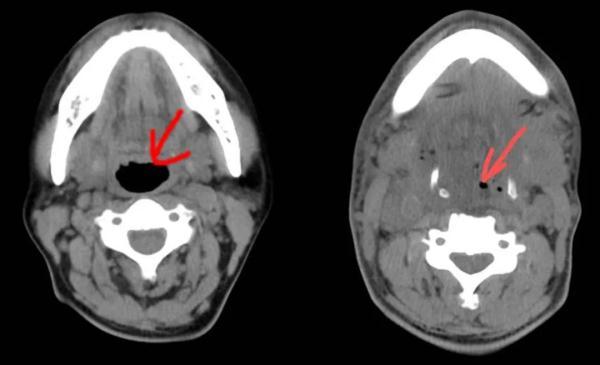

急診CT影像片子里,蔣先生的咽喉、口底、頜下等部位有大量積液和積氣,氣管已被擠得“消失”。

“兇險(xiǎn),患者是走了一趟鬼門關(guān)?!迸_州恩澤醫(yī)療中心(集團(tuán))恩澤醫(yī)院口腔部主治醫(yī)師陳申國會診后說,這是典型的牙齒發(fā)炎導(dǎo)致的口底多間隙感染,這種病發(fā)展迅速,處理不當(dāng)會有很高的致死率。現(xiàn)在患者雖然做了氣管切開,沒有窒息的危險(xiǎn),但還是需要盡快排膿引流,并且要阻止感染進(jìn)一步擴(kuò)散,以免給后續(xù)救治帶來更大麻煩。

蔣先生的病情一天天好轉(zhuǎn),術(shù)后第五天的CT影像片子里,終于出現(xiàn)了氣管的蹤跡,雖然只有黑豆那么大。能自主呼吸,意味著能拔氣切插管了。

左圖為正常氣管,右圖為患者術(shù)后第五天的氣管